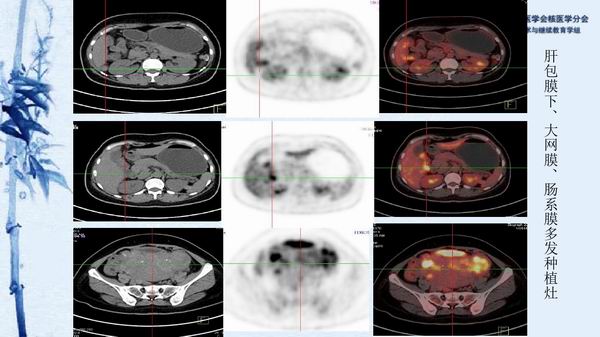

病例45:卵巢结节性甲状腺肿伴乳突状癌-【CSNM继教学组】农天雷 柳州市柳铁中心医院